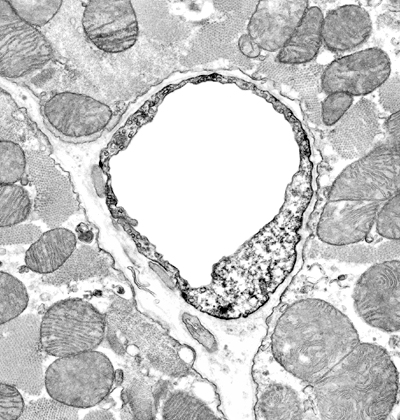

Fig 3: Myocardial capillary producing NO

Large version, coronary NOS© A Loesch